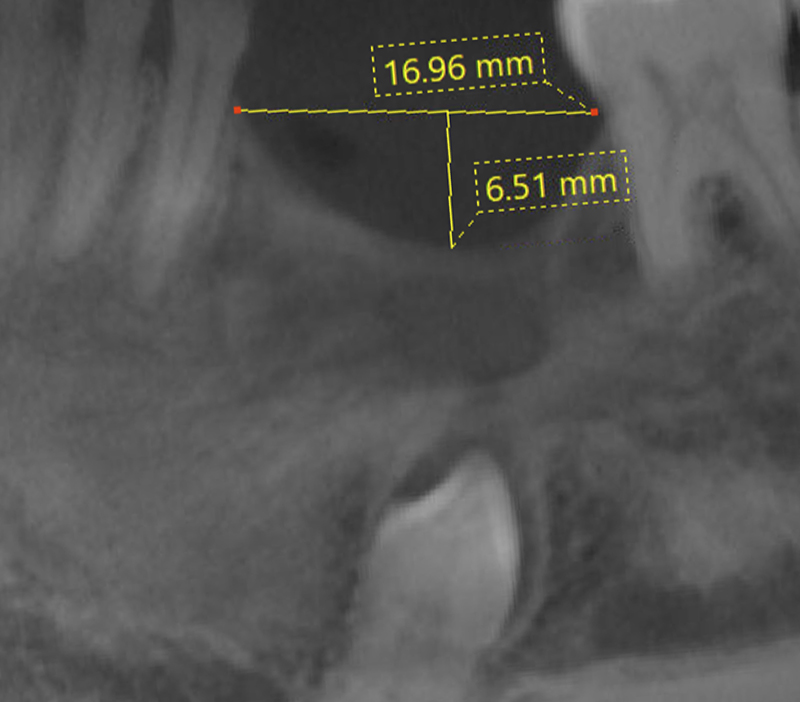

Compte tenu de la perte osseuse associée à cette lésion (défaut transversal supérieur à 10mm, longitudinal de 17mm et vertical de 6,5mm), il est proposé au patient une greffe osseuse autogène selon la technique des lames corticales décrite par Fouad Khoury(9).

Cette technique opératoire consiste à positionner un fragment osseux prélevé en intra-oral au niveau d’un site receveur, afin de reconstruire la crête osseuse prélèvement osseux intra-oral d’un bloc cortico-spongieux d’origine rétro-molaire. L’os particulaire cortico-spongieux est récupéré à la fois au niveau du bloc osseux et au niveau du site donneur. Les lames osseuses sont ensuite ostéosynthésées à l’aide de micro-vis et la partie interne du coffrage est remplie d’os particulaire autogène.